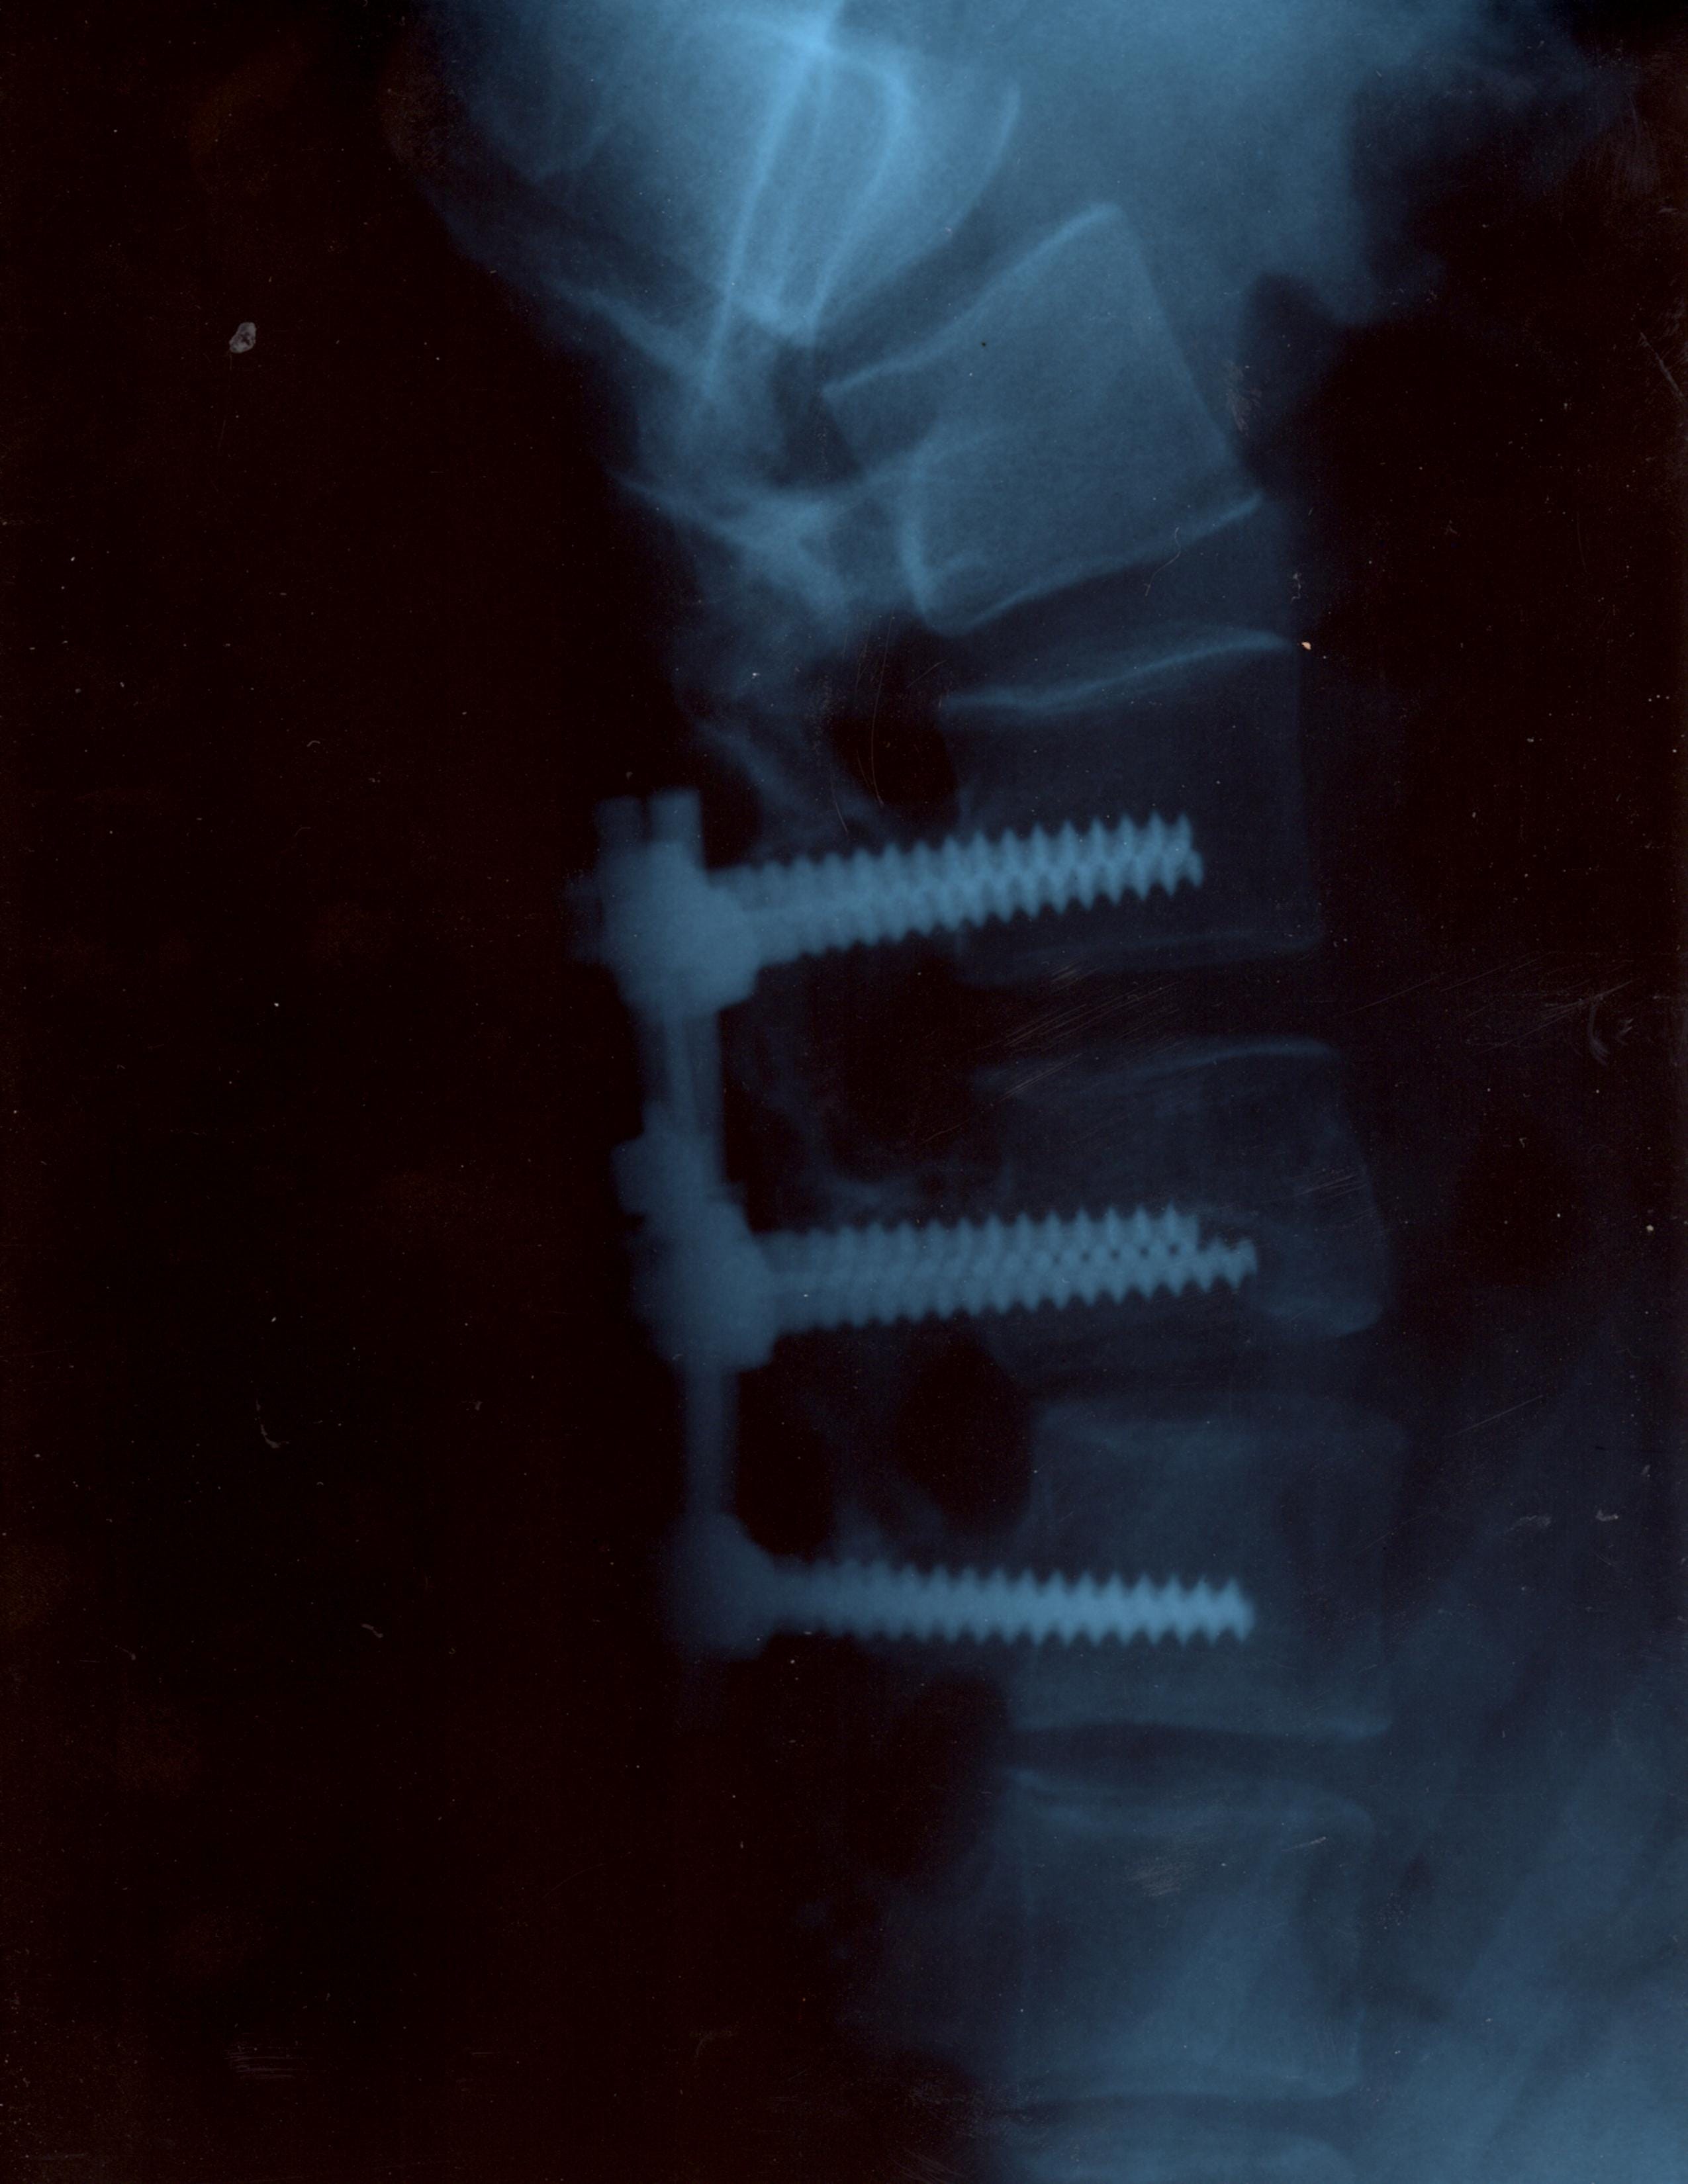

About 20 years before I served at Elk Neck State Park, in my naïveté I was involved in an accident involving snow, ice, inertia, and unfortunately gravity - which resulted in three fused vertebrae. The surgeon said I was 2 centimeters away from being paralyzed from the waist down.